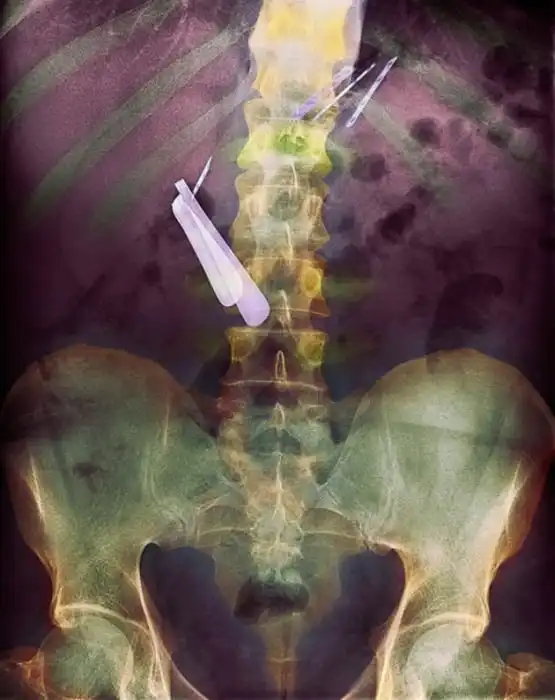

Жуткие рентгеновские снимки

Порой даже не верится, с какими странными и необычными повреждениями в травматологию могут поступить пострадавшие. Всю эпичность профессии врачей травматологии могут с легкостью подтвердить рентгеновские снимки.